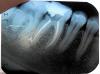

Что происходит вообще с моим зубом? Как это лечить? Снимки прилагаю. 36 зуб.

В обоих передних каналах сломаны инструменты. Видимо, сломаны в начале обработки, пульпа там осталась. В вашем городе работает замечательный доктор Дмитрий Кудряшов-ему такие случаи удаётся побороть. Найдите его поиском-если не получится, напишите мне, я Вас с ним сведу. У него это недёшево, но надежно.

Значит, что сломались кончики инструментов, которыми чистили каналы и остались в каналах. И каналы в этой части остались недочищенными, с микробами, поэтому болит. Прислушайтесь к совету Scrabble